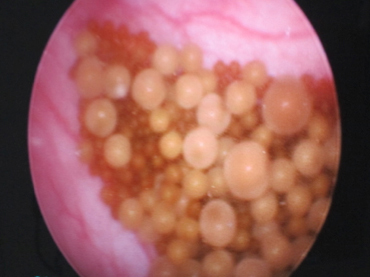

膀胱結石があり、摘出の際に硬性鏡で観察しながら取り出しました。 小さな傷で取り出せるため、とても低侵襲です。

膀胱内のポリープを確認し、膀胱の部分切除を行いました。 傷をつける前に観察することで出血がなく、明瞭な視野でポリープの確認が可能です。